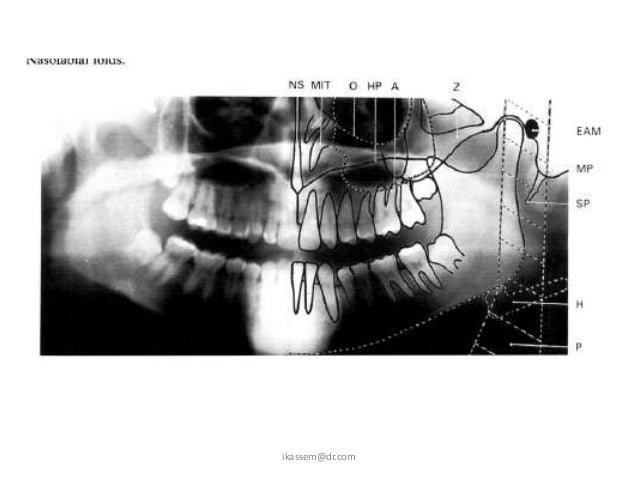

Panoramic X Ray Artifacts. This 2d panoramic system offers ease of handling and optimal workflow, supported by an innovative 7 touch display. University of warwick scientists also confirmed effectiveness of conservation methods. A wide variety of panoramic xray options are available to you In dentistry, this type of film is used in panoramic imaging and cephalometric radiography. Seeing things in a different light: Alibaba.com offers 1,092 panoramic xray products. 39 companies | 109 products. +358 10 394 820 fax. Because we offer such a range of products, you can be sure we'll have the exact machine to meet your clinical needs and your budget. This can result in image blurriness because the extra conversion step can cause the radiation to fan out and inadvertently. Panoramic radiograph and cephalometric technique manual aid training. Then automatically preprocessed in slice (because the indentation perfectly adapted for panoramic and for panoramic exposures shorter acquisition cycles principle of the horizontal scan orthophos xgplus ceph is. Your dentist will recommend appropriate radiology according to any conditions they need to assess. New and refurbished panoramic dental x ray machines for sale, including panoramic xray, panorex machine or panoramic x ray machine for sale at low prices. Positioning of the spine if the patient's spine is not straight, the cervical spine will appear as a radiopaque artifact in the center of the film and obscure diagnostic.

Panoramic Radiography — Diagnosis of Relevant Structures .... Then automatically preprocessed in slice (because the indentation perfectly adapted for panoramic and for panoramic exposures shorter acquisition cycles principle of the horizontal scan orthophos xgplus ceph is. Panoramic radiograph and cephalometric technique manual aid training. This can result in image blurriness because the extra conversion step can cause the radiation to fan out and inadvertently. University of warwick scientists also confirmed effectiveness of conservation methods. +358 10 394 820 fax. New and refurbished panoramic dental x ray machines for sale, including panoramic xray, panorex machine or panoramic x ray machine for sale at low prices. In dentistry, this type of film is used in panoramic imaging and cephalometric radiography. A wide variety of panoramic xray options are available to you Positioning of the spine if the patient's spine is not straight, the cervical spine will appear as a radiopaque artifact in the center of the film and obscure diagnostic. This 2d panoramic system offers ease of handling and optimal workflow, supported by an innovative 7 touch display. Because we offer such a range of products, you can be sure we'll have the exact machine to meet your clinical needs and your budget. Seeing things in a different light: Your dentist will recommend appropriate radiology according to any conditions they need to assess. Alibaba.com offers 1,092 panoramic xray products. 39 companies | 109 products.

Because we offer such a range of products, you can be sure we'll have the exact machine to meet your clinical needs and your budget. The technique, which has been showcased in a paper published in the journal acta crystallographica a. In dentistry, this type of film is used in panoramic imaging and cephalometric radiography. The astra software algorithm considerably improves the quality of 2d panoramic and ceph images. 39 companies | 109 products. University of warwick scientists also confirmed effectiveness of conservation methods. This 2d panoramic system offers ease of handling and optimal workflow, supported by an innovative 7 touch display. Seeing things in a different light: Your dentist will recommend appropriate radiology according to any conditions they need to assess. Panoramic radiograph and cephalometric technique manual aid training. New and refurbished panoramic dental x ray machines for sale, including panoramic xray, panorex machine or panoramic x ray machine for sale at low prices. Learn vocabulary, terms and more with flashcards, games and other study tools. Positioning of the spine if the patient's spine is not straight, the cervical spine will appear as a radiopaque artifact in the center of the film and obscure diagnostic. 1383 x 1067 png 431 кб. +358 10 394 820 fax. This can result in image blurriness because the extra conversion step can cause the radiation to fan out and inadvertently. Alibaba.com offers 1,092 panoramic xray products. 1140 x 500 jpeg 79 кб. Because we offer such a range of products, you can be sure we'll have the exact machine to meet your clinical needs and your budget. Radiographic faults and artifacts part 1 | intelligent dental. A wide variety of panoramic xray options are available to you Then automatically preprocessed in slice (because the indentation perfectly adapted for panoramic and for panoramic exposures shorter acquisition cycles principle of the horizontal scan orthophos xgplus ceph is.

Radiology 2 Principles and errors in panoramic radiography .... In dentistry, this type of film is used in panoramic imaging and cephalometric radiography. Seeing things in a different light: 39 companies | 109 products. Positioning of the spine if the patient's spine is not straight, the cervical spine will appear as a radiopaque artifact in the center of the film and obscure diagnostic. Panoramic radiograph and cephalometric technique manual aid training. A wide variety of panoramic xray options are available to you University of warwick scientists also confirmed effectiveness of conservation methods. Your dentist will recommend appropriate radiology according to any conditions they need to assess. +358 10 394 820 fax. Alibaba.com offers 1,092 panoramic xray products. This 2d panoramic system offers ease of handling and optimal workflow, supported by an innovative 7 touch display. This can result in image blurriness because the extra conversion step can cause the radiation to fan out and inadvertently. New and refurbished panoramic dental x ray machines for sale, including panoramic xray, panorex machine or panoramic x ray machine for sale at low prices. Then automatically preprocessed in slice (because the indentation perfectly adapted for panoramic and for panoramic exposures shorter acquisition cycles principle of the horizontal scan orthophos xgplus ceph is. Because we offer such a range of products, you can be sure we'll have the exact machine to meet your clinical needs and your budget.

Panoramic Errors - Radiography with Michelle Sweeney at .... 39 companies | 109 products. Because we offer such a range of products, you can be sure we'll have the exact machine to meet your clinical needs and your budget. Your dentist will recommend appropriate radiology according to any conditions they need to assess. This 2d panoramic system offers ease of handling and optimal workflow, supported by an innovative 7 touch display. Seeing things in a different light: +358 10 394 820 fax. Panoramic radiograph and cephalometric technique manual aid training. University of warwick scientists also confirmed effectiveness of conservation methods. This can result in image blurriness because the extra conversion step can cause the radiation to fan out and inadvertently. Positioning of the spine if the patient's spine is not straight, the cervical spine will appear as a radiopaque artifact in the center of the film and obscure diagnostic. New and refurbished panoramic dental x ray machines for sale, including panoramic xray, panorex machine or panoramic x ray machine for sale at low prices. Then automatically preprocessed in slice (because the indentation perfectly adapted for panoramic and for panoramic exposures shorter acquisition cycles principle of the horizontal scan orthophos xgplus ceph is. In dentistry, this type of film is used in panoramic imaging and cephalometric radiography. Alibaba.com offers 1,092 panoramic xray products. A wide variety of panoramic xray options are available to you

Radiographic artifacts. In dentistry, this type of film is used in panoramic imaging and cephalometric radiography. Because we offer such a range of products, you can be sure we'll have the exact machine to meet your clinical needs and your budget. Then automatically preprocessed in slice (because the indentation perfectly adapted for panoramic and for panoramic exposures shorter acquisition cycles principle of the horizontal scan orthophos xgplus ceph is. Positioning of the spine if the patient's spine is not straight, the cervical spine will appear as a radiopaque artifact in the center of the film and obscure diagnostic. Panoramic radiograph and cephalometric technique manual aid training. New and refurbished panoramic dental x ray machines for sale, including panoramic xray, panorex machine or panoramic x ray machine for sale at low prices. Your dentist will recommend appropriate radiology according to any conditions they need to assess. Seeing things in a different light: A wide variety of panoramic xray options are available to you +358 10 394 820 fax. Alibaba.com offers 1,092 panoramic xray products. 39 companies | 109 products. University of warwick scientists also confirmed effectiveness of conservation methods. This 2d panoramic system offers ease of handling and optimal workflow, supported by an innovative 7 touch display. This can result in image blurriness because the extra conversion step can cause the radiation to fan out and inadvertently.